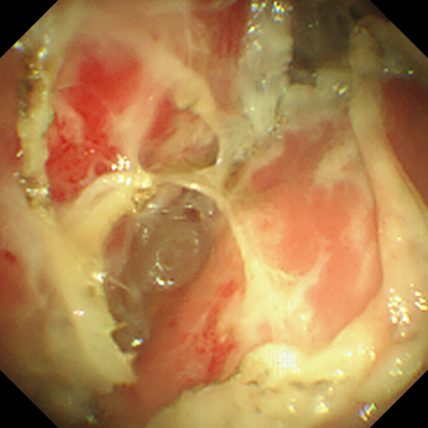

罗少华主任带领呼吸内镜介入团队,为患者行经胸腔镜下胸膜活检术+胸膜黏连烙断术(见图3-5),过程顺利,呼吸困难明显减轻,术后予以胸腔闭式引流术+胸腔内纤溶性药物注射,复查胸片及胸腔积液超声,包裹性胸腔积液情况明显减轻(见图6)。

图5:术中胸腔镜下行胸膜粘连激光烙断术

图6:术后见胸膜粘连被激光烙断